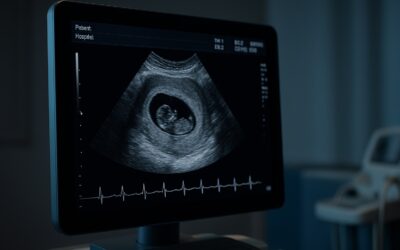

Qué muestra la ecografía en las primeras semanas La Ecografía obstétrica es una herramienta clave...

Indispensable para el diagnóstico de condiciones ginecológicas y el monitoreo temprano del embarazo.